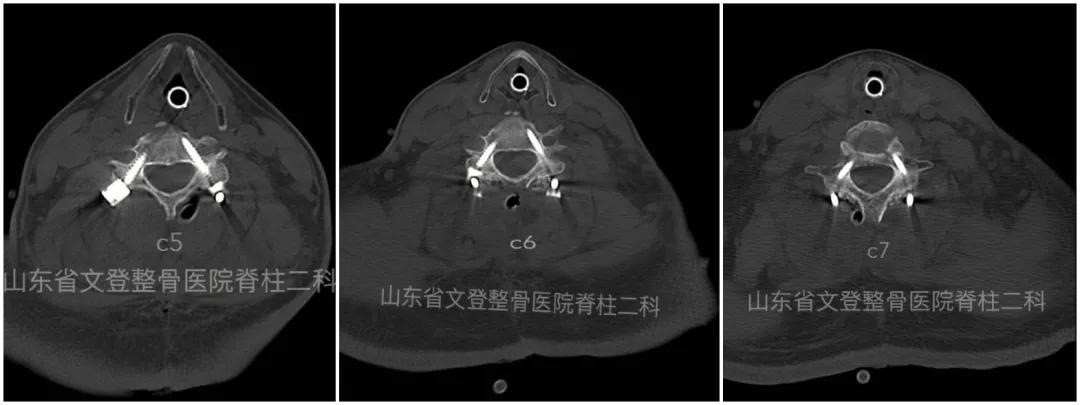

术前颈椎CT 术后颈椎CT解剖复位

术后C5-C7 椎弓根钉

术前颈椎MRI 术后颈椎MRI脊髓无任何压迫